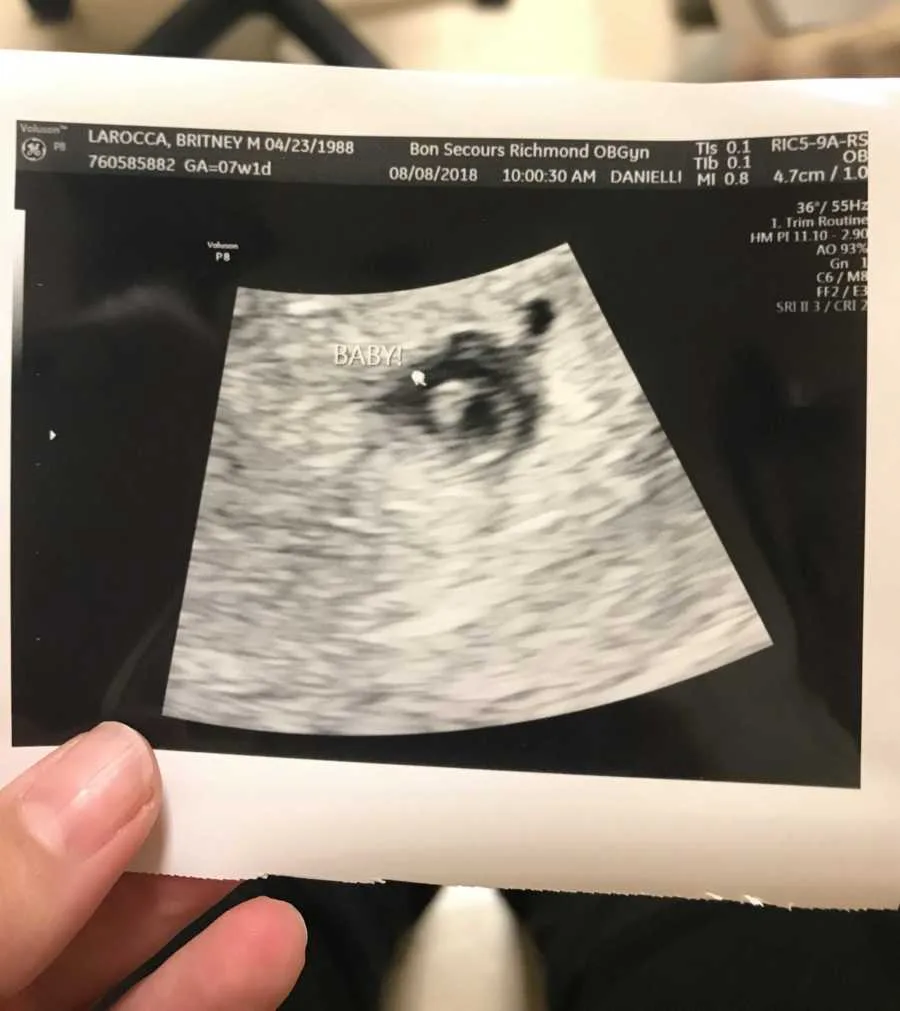

Motherhood had already changed her, even without a baby in her arms. The miscarriage left invisible bruises that would take months to fade. Her anxiety deepened, and she stopped her medication, trying to heal naturally, searching for control in a situation that had taken so much of it away. She told herself she would try again, that hope still mattered. By July, a new pregnancy test turned positive. This time, fear replaced excitement. Pregnancy, once joyful, now felt fragile. She went through appointments and ultrasounds, her heart clinging to cautious optimism. But soon, the cramping and bleeding returned. One sac stopped developing, and then the heartbeat disappeared altogether. Another miscarriage. Another goodbye.